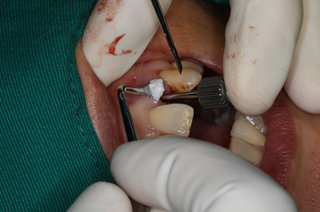

麦芽口腔硕博种牙团在了解到邓女士的情况后,对口腔全景ct深度分析,邓女士的剩下的牙齿残根已经无法再满足做普通的牙齿的美学修复,只有拔除剩下的残根,做种植牙才是最佳的牙齿修复的方式。麦芽硕博团为邓女士选择麦芽数字化生物种植牙保证口腔功能重建和舒适修复的同时,兼顾口腔美学修复,既能快速修复牙齿,恢复咀嚼,同时能够达到较好的美观程度,术中采用STA美国微痛麻醉,确保了手术全程的舒适度,且采用数字化3D种植导板技术,能够更加准确、更加快速找到最佳植入位置,有效避免手术过程遭受痛苦,保证了手术成功率。

安装种植体